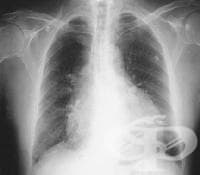

Пример за такива изследвания са кръвно-газовият анализ след диагностициран пневмоторакс с рентгеново изследване или провеждане на биопсия за определяне на степен на злокачественост (малигненост).